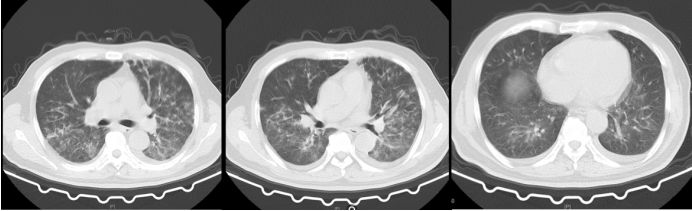

4月2日:外院胸部CT检查示:双上肺及下叶背段斑片状渗出(图1)

图1  外院胸部CT(2023-04-02)

复查胸部CT:双肺支气管血管束增粗,见多发结节影、斑片影及磨玻璃密度影。双肺见索条影;肺门、纵隔未见肿大淋巴结;双侧少量胸腔积液。心包少量积液(图2)

图2  外院胸部CT(2023-04-07)